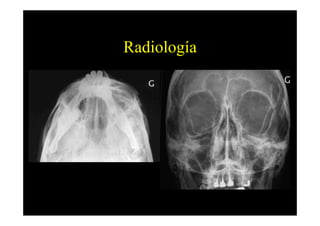

Radiología